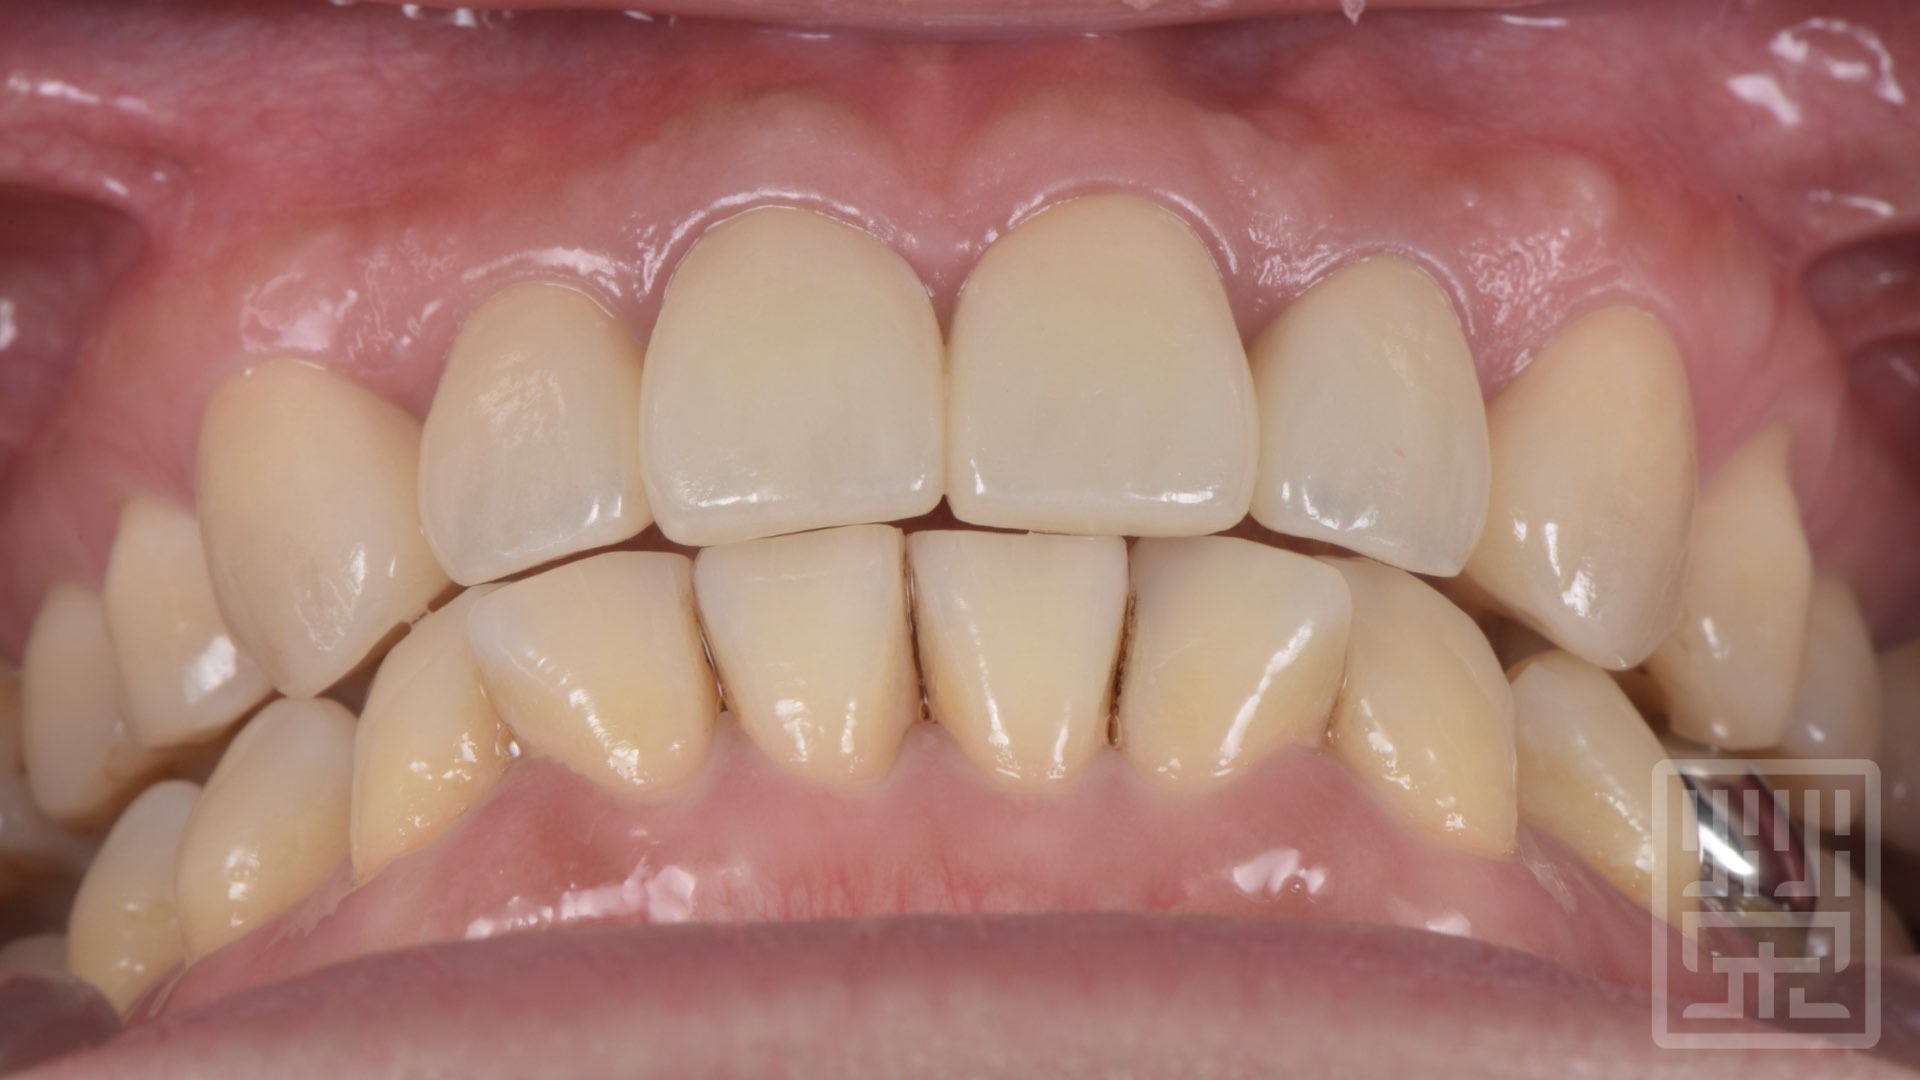

植牙全瓷冠修復

保護性咬合